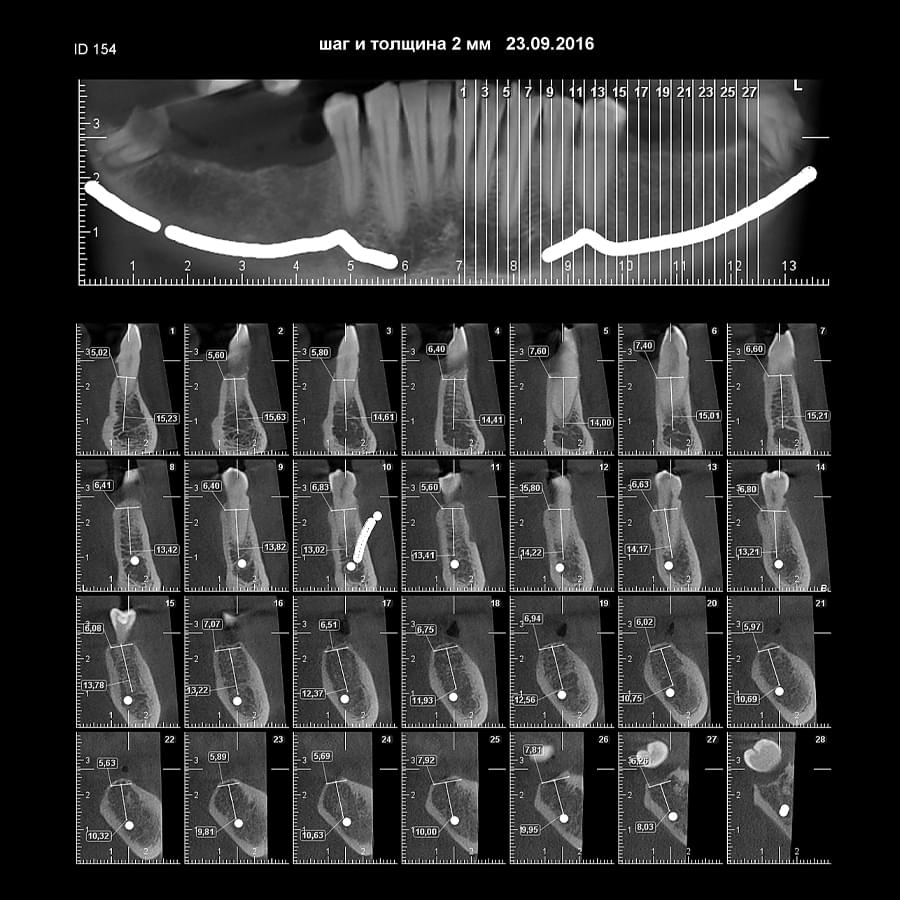

Коли коріння «ховає сюрпризи» - Корені зубів часто мають складну кривизну, гачкоподібні закручення або розгалуження, які на звичайному 2D-знімку накладаються один на одного, створюючи ілюзію прямого каналу. На плоскій картинці неможливо побачити реальний об'єм та напрямок вигину, що критично важливо при видаленні «зубів мудрості» або ендодонтичному лікуванні. КТ MyRay дає змогу лікарю заздалегідь побачити 3D-геометрію кожного кореня, оцінити його близькість до нижньощелепного нерва чи гайморової пазухи та підібрати правильну тактику роботи. Це мінімізує ризики поломки інструменту в каналі або травмування сусідніх структур, перетворюючи складну хірургію на прогнозовану процедуру.

При плануванні імплантації лікарю важливо знати дві речі: об'єм кістки та точне розташування нервів.

КТ дозволяє провести віртуальну операцію: встановити імплант у програмі, виключивши будь-які ризики травмування пацієнта.